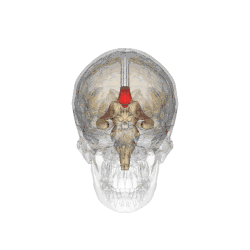

![]() Corpus callosum from above, front part at the top of the image | |

A number of separate nerve tracts, classed as subregions of the corpus callosum, connect different parts of the hemispheres. The main ones are known as the genu, the rostrum, the trunk or body, and the splenium.[4]

The corpus callosum has four main parts – individual nerve tracts that connect different parts of the hemispheres. These are the rostrum, the genu, the trunk or body, and the splenium.[4] Fibres from the trunk and the splenium, known together as the tapetum ("carpet"), form the roof of each lateral ventricle.[6]

On either side of the corpus callosum, the fibers radiate in the white matter and pass to the various parts of the cerebral cortex; those curving forward from the genu into the frontal lobes constitute the forceps minor (also forceps anterior) and those curving backward from the splenium into the occipital lobes, the forceps major (also forceps posterior).[4] Between these two parts is the main body of the fibers, which constitute the tapetum and extend laterally on either side into the temporal lobe, and cover in the central part of the lateral ventricle. The tapetum and anterior commissure share the function of connecting left and right temporal lobes.